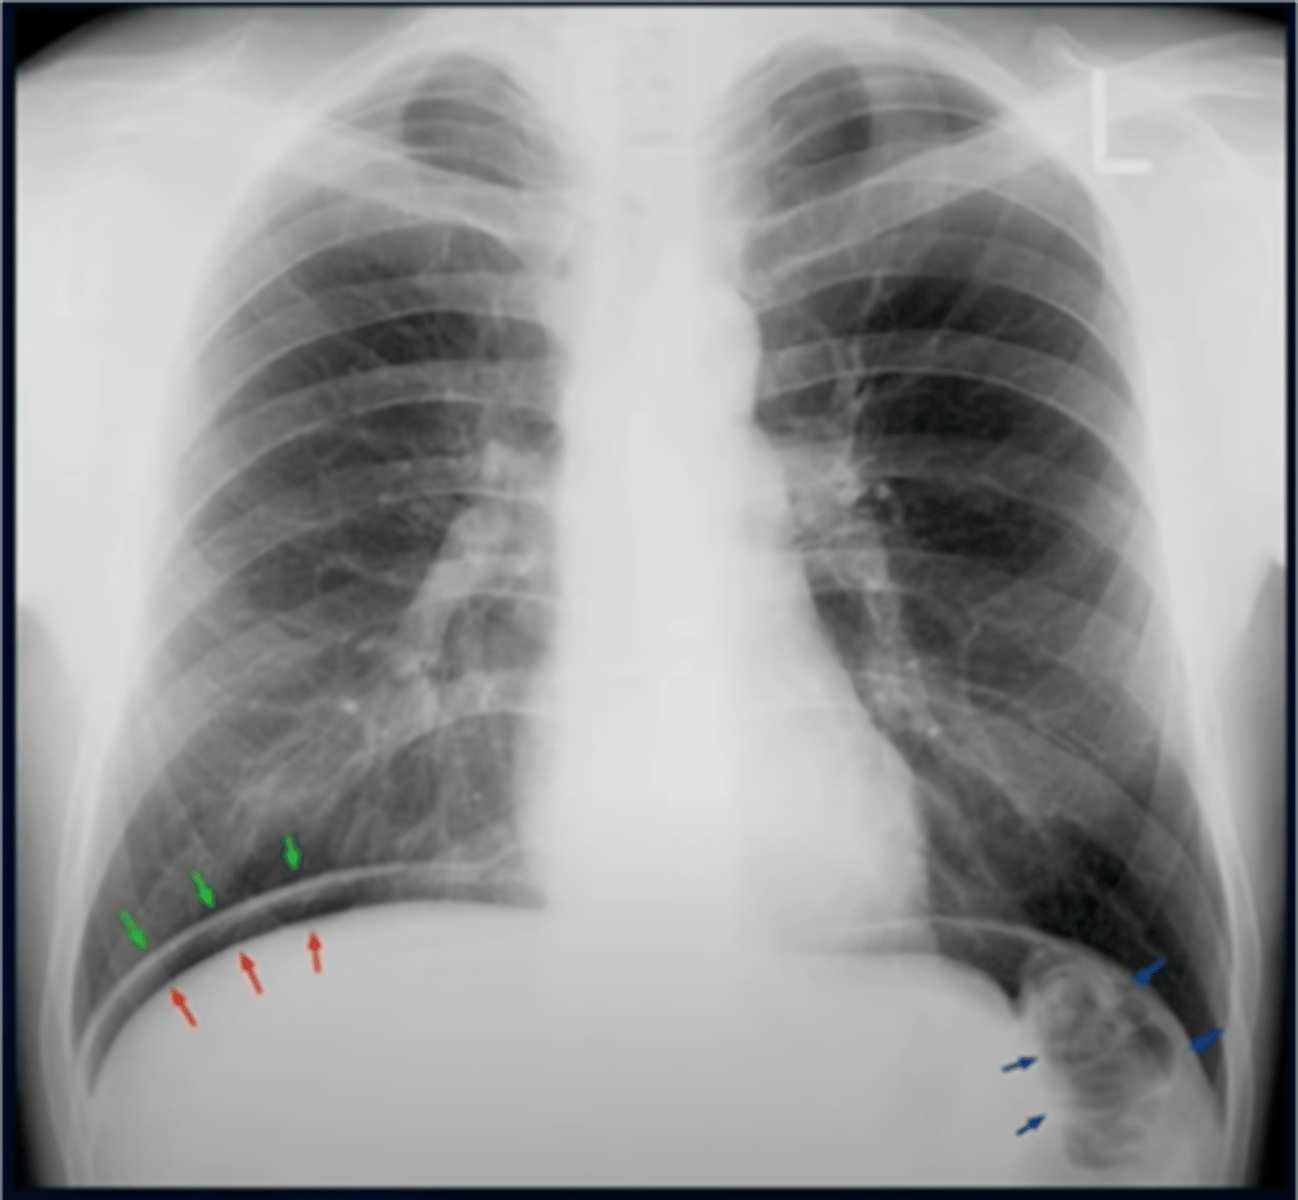

free air (pic 1)

Free air (pic 2)

free air under the diaphragm (indicative of pneumoperitoneum)